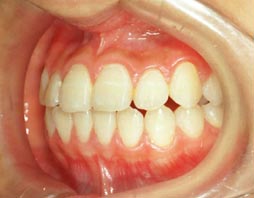

2.上顎前突(出っ歯) 上の前歯がかなり出ていています

治療前

治療後